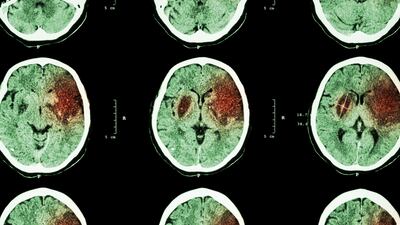

The first reported analysis demonstrating a patient-level dose response with Novocure’s Tumor Treating Fields therapy is now published. The post-hoc analysis of the EF-14 trial showed higher doses of Tumor Treating Fields improved survival in newly diagnosed glioblastoma patients.